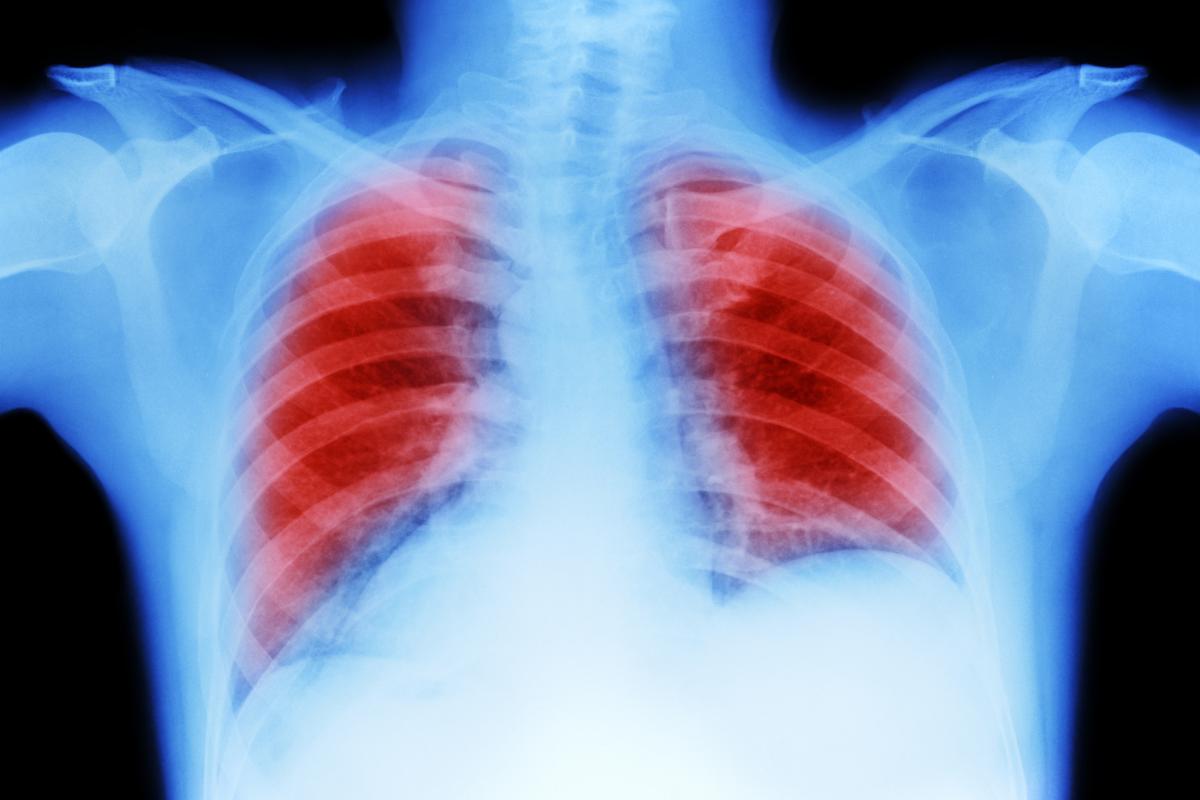

"Afortunadamente, mi médico me envió a hacerme una radiografía y análisis de sangre, y esa tarde recibí una llamada diciendo que se había encontrado una 'masa' en mi pulmón izquierdo", ha contado la mujer al tabloide británico.